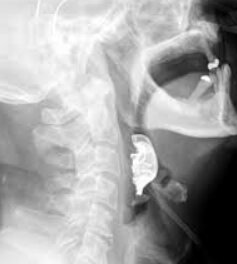

Obyvatel Velké Británie byl hospitalizován. Byl mu udělán rentgen, který ukázal, že mu v hrdle uvízla protéza.

Lékaři provedli nouzovou operaci k odstranění cizího předmětu.